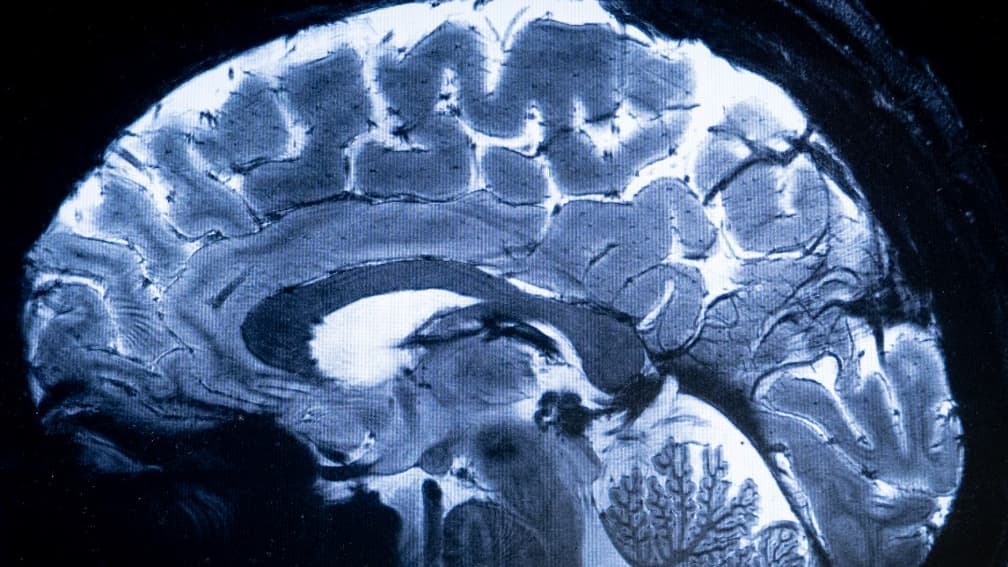

Il loro robot assomiglia a un piccolo lombrico flessibile, dotato di un micro-propulsore che ruota in una direzione per avanzare e nell'altra per retrocedere. Basta un piccolo foro di 3 millimetri nel cranio: il robot si infila nel cervello, guidato da un neurochirurgo tramite risonanza magnetica, come un GPS.